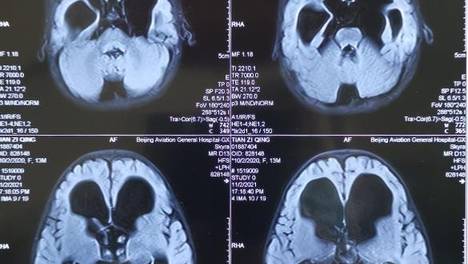

诊断依据患者有开放性颅脑损伤、脑内出血、颅脑手术、开放性颅骨骨折病史,颅内出血后可造成脑脊液吸收及循环通路障碍,进一步脑脊液在各脑池蓄积,患者有慢性颅内压增高症状、反复脑脊液异常。患者目前脑出血、继发脑积水合并中枢神经系统感染,给予抗感染